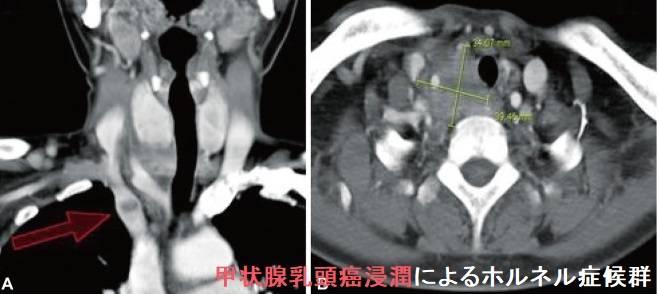

甲状腺癌浸潤によるホルネル(ホルナー、Horner)症候群

甲状腺乳頭癌浸潤によるホルネル(ホルナー、Horner)症候群[Brain Tumor Res Treat. 2014 Oct;2(2):132-7.]